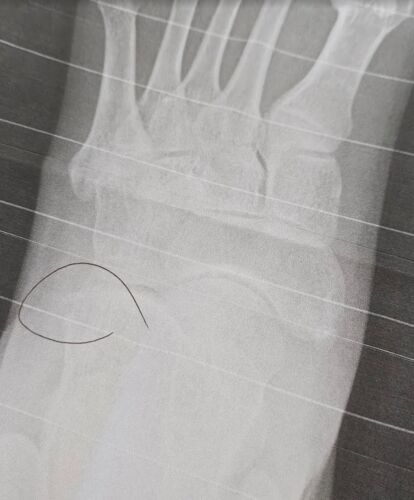

4年ぶりに足を捻った日記

1日目 木 2日目 金 3日目 土 4日目 日 5日目 月 6日目 火 1日目 木 木曜日出社中のお昼休みにガウシアン撮影しようと思ってスマホ構えながら歩いてたら段差に気づかず転んで左足をガッツリ捻った。右膝は擦りむいた 足を捻るのは四年ぶり! bibinbaday.haten…